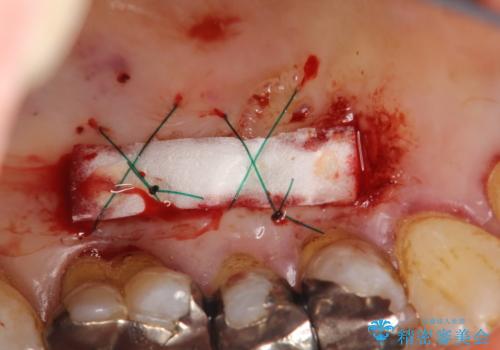

今回のケースでは小臼歯2本分の幅に渡って丈夫な歯肉を確保させるため、オペのデザイン上、横に幅広く均一な結合組織を採取する必要がありました。そのため、トラップドア方式で内部の組織をえぐって採取する術式は使わず、上顎歯肉の表層から結合組織部までを含む部分までを遊離歯肉採取の要領でやや深めに採取し、表層部分をトリミングする事で均一な厚みの結合組織を採取しました。この術式の利点として、上顎の歯肉に過度に深い侵襲を与える事がないため、組織採取部の術後の治癒が非常に早く、術後の不快症状も少なくて済む事が挙げられます。